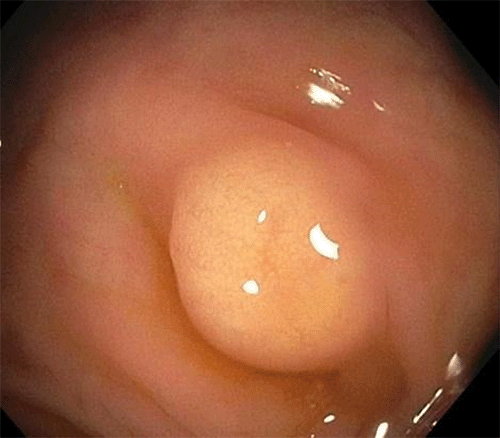

Final anatomic pathology revealed the following: 5 × 3 mm granular cell tumor of the submucosa at the cecum without invasion of the muscularis propria (Figure 2), IHC staining positive for S100 (Figure 3A) and CD68 (Figure 3B), 28 reactive lymph nodes without evidence of metastasis. Small bowel, colonic, and soft tissue margins were tumor-free.

Figure 2. Two H&E Stains. Published with Permission

B. 400x magnification: granular cytoplasm

The diagnosis of GCT depends on histopathology with a variable architecture ranging from small and well-circumcised nodules to larger and poorly circumscribed lesions.2,3 They may sometimes display an infiltrative property with satellite nodules as well.2,3 GCT cells are typically rounded epithelioid with a diffusely granular eosinophilic cytoplasm (Figure 3). The cytoplasm of the tumor cells accumulates secondary lysosomes responsible for the granular appearance.4 The lysosomes stain with PAS and are diastase resistant.4 IHC positivity for CD68 and neural marker S100 supports the diagnosis of GCT.2,4,9 Despite a large amount of IHC studies, the histogenesis of GCTs has not yet been fully elucidated. However, IHC reactivity with S100, myelin, vimentin, neuron-specific enolase, calretinin, and CD-68 suggests derivation from Schwann cells.2,4,9